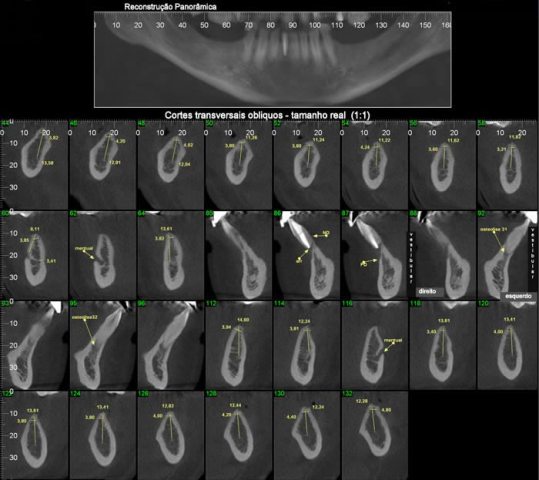

Nos softwares há ferramentas que permitem a reconstrução e a obtenção de novos cortes que mostram imagens de uso pontual na odontologia como os cortes transversais e longitudinais.

Os cortes transversais são cortes perpendiculares ao arco da maxila e mandíbula.

Na reconstrução panorâmica aparece uma régua no limite inferior que serve de localização para os cortes transversais.

Os cortes longitudinais são cortes no sentido vestíbulo lingual ou palatino, perpendiculares a uma reta traçada sobre o dente ou a área em questão.

Dente 47 e 48 retidos, em posição mésio horizontal, sobrepostos com raízes superpostas ao canal mandibular. Ao exame tomográfico identifica-se o canal passando rechaçado entre os ápices do 48 e a cortical vestibular e passando entre as duas raízes mesiais do dente 47.